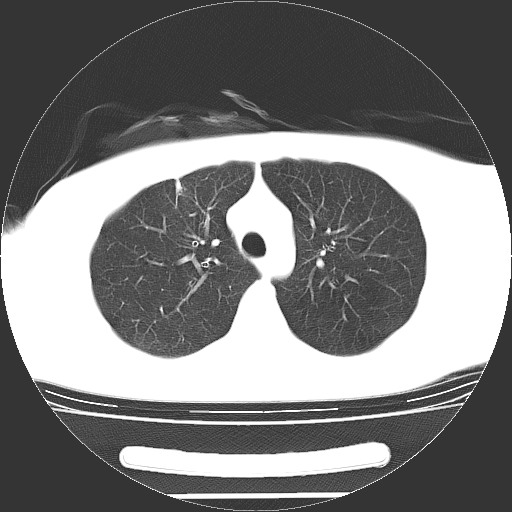

标题: CT19767:男,20岁,右侧气胸行闭式引流术后五天CT检查。 [打印本页]

男,20岁,右侧气胸行闭式引流术后五天ct检查看肺内是否有肺大泡,纵隔窗未见异常,未上传。

1)右侧胸腔闭式引流术后导管留置。2)右肺未见肺大泡。

未见肺大泡,还有微量气体。